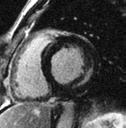

The cardiac MRI scan at the left reveals an enlarged heart, left ventricular hypertrophy (LVH) and scar tissue in the left ventricle wall as a result of Fabry disease. Periodic cardiac MRI scans at 18 months on enzyme replacement therapy (ERT), 24 months on ERT, and 30 months on ERT indicate significant reduction in heart volume and left ventricle wall thickness improving with each subsequent scan. The image at the right shows the same approximately 50-year-old male's heart with normal heart function despite reduced yet persistent LVH. This individual had been on ERT for 5 years at the time of this entry.